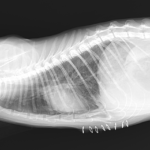

保護した猫さんの呼吸が早いかも??? かかりつけの先生に相談されたようです。エックス線検査で横隔膜ヘルニアが確定されました。外科的な対応を希望され来院されました。肝臓のほとんどが胸腔内にヘルニア(逸脱)しており、開腹アプローチで横隔膜を整復しました。正しい位置に臓器が戻ったので、これからは呼吸が楽になります。